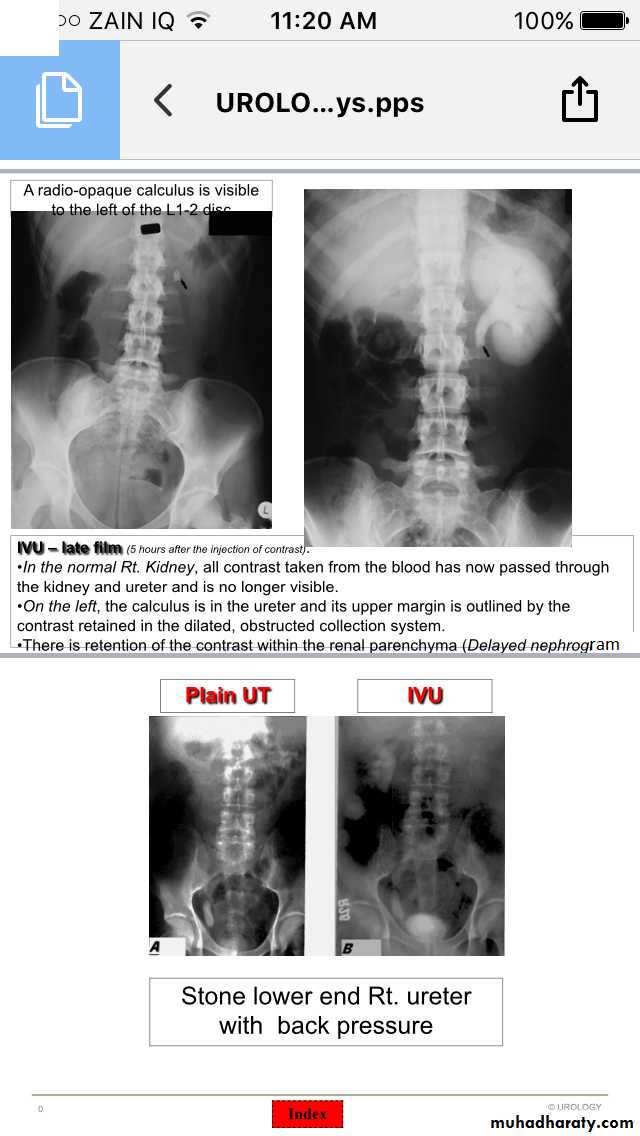

Ureteric stones